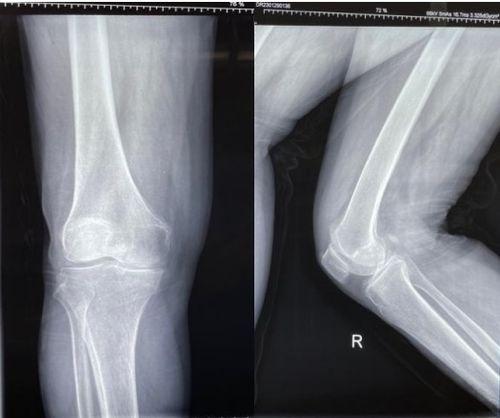

首先,得知道,膝盖手术可不是随便一剪子就能解决的。它主要分为两大类:关节镜手术和开放式手术。

关节镜手术,听起来是不是有点像科幻电影里的高科技?其实,它就是通过一个小小的镜子,医生可以清楚地看到你的膝盖内部,然后进行修复或清理。这种手术创伤小,恢复快,是现在比较流行的方法。

而开放式手术,顾名思义,就是医生会在你的膝盖处开一个较大的切口,直接进行手术。这种手术适用于一些比较复杂的病例,但恢复时间相对较长。